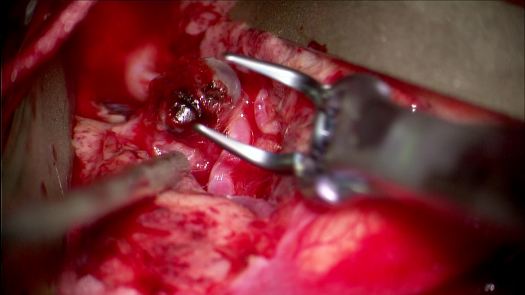

Clipping di aneurisma complesso M1-M2 di sinistra – ricostruzione biforcazione arteria cerebrale media

Aneurisma Biforcazione ACM – Vito Fiorenza